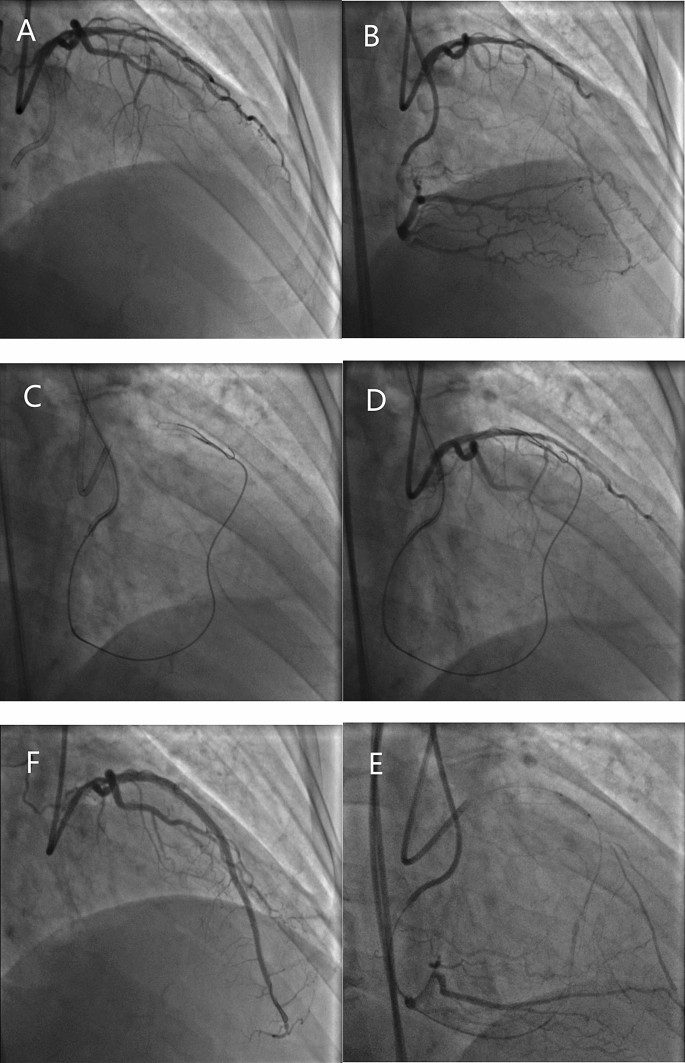

Conventional antegrade wire escalation is reportedly as the most commonly used CTO crossing technique (in 67–77% of cases)13,14, especially for less complex occlusions. However, a conventional approach is unsuitable for long, calcified, and tortuous occlusions. In the last decade, there has been a marked increase in the use of the dissection-reentry strategy for PCI of CTO with reported CTO recanalization rates of more than 80%15,16,17. Dissection-reentry techniques involve crossing the occlusion in the subintimal space followed by reentry into the true lumen using a guidewire or dedicated system. However, this technique involves extensive dissection and intramural hematoma with compression of ostial SB and results in loss of SB. Furthermore, implantation of a stent in the subintimal space often leads to SB occlusion (Fig. 1). In our study, use of a dissection-reentry technique (antegrade or retrograde) was an independent predictor of SB occlusion (OR 4.25; 95% CI 1.29–13.99; P = 0.017) and SB occlusion was more common (71.4%) after stent implantation in occlusion group. A further development in this field is the advent of devices specifically designed to limit the extent of dissection and minimize vessel trauma, thereby preserving the SB (for example, use of special reentry devices, such as the CrossBoss-Stingray system or the guideliner reverse controlled antegrade and retrograde subintimal tracking)18,19.

SB was obstructed during recanalization of CTO using RDR technique A CTO in the left anterior descending artery with a significant diagonal branch in the proximal cap. (B) Distal filling by contralateral collaterals from the right coronary artery. (C) Retrograde approach through a septal channel. (D) RDR technique crossed to the true lumen. (E) Balloon dilation of the main vessel without SB protection. (F) After implantation of the main vessel stents, the SB was obstructed with TIMI flow grade 1. CTO, chronic total occlusion; RDR, retrograde dissection and reentry; SB, side branch.